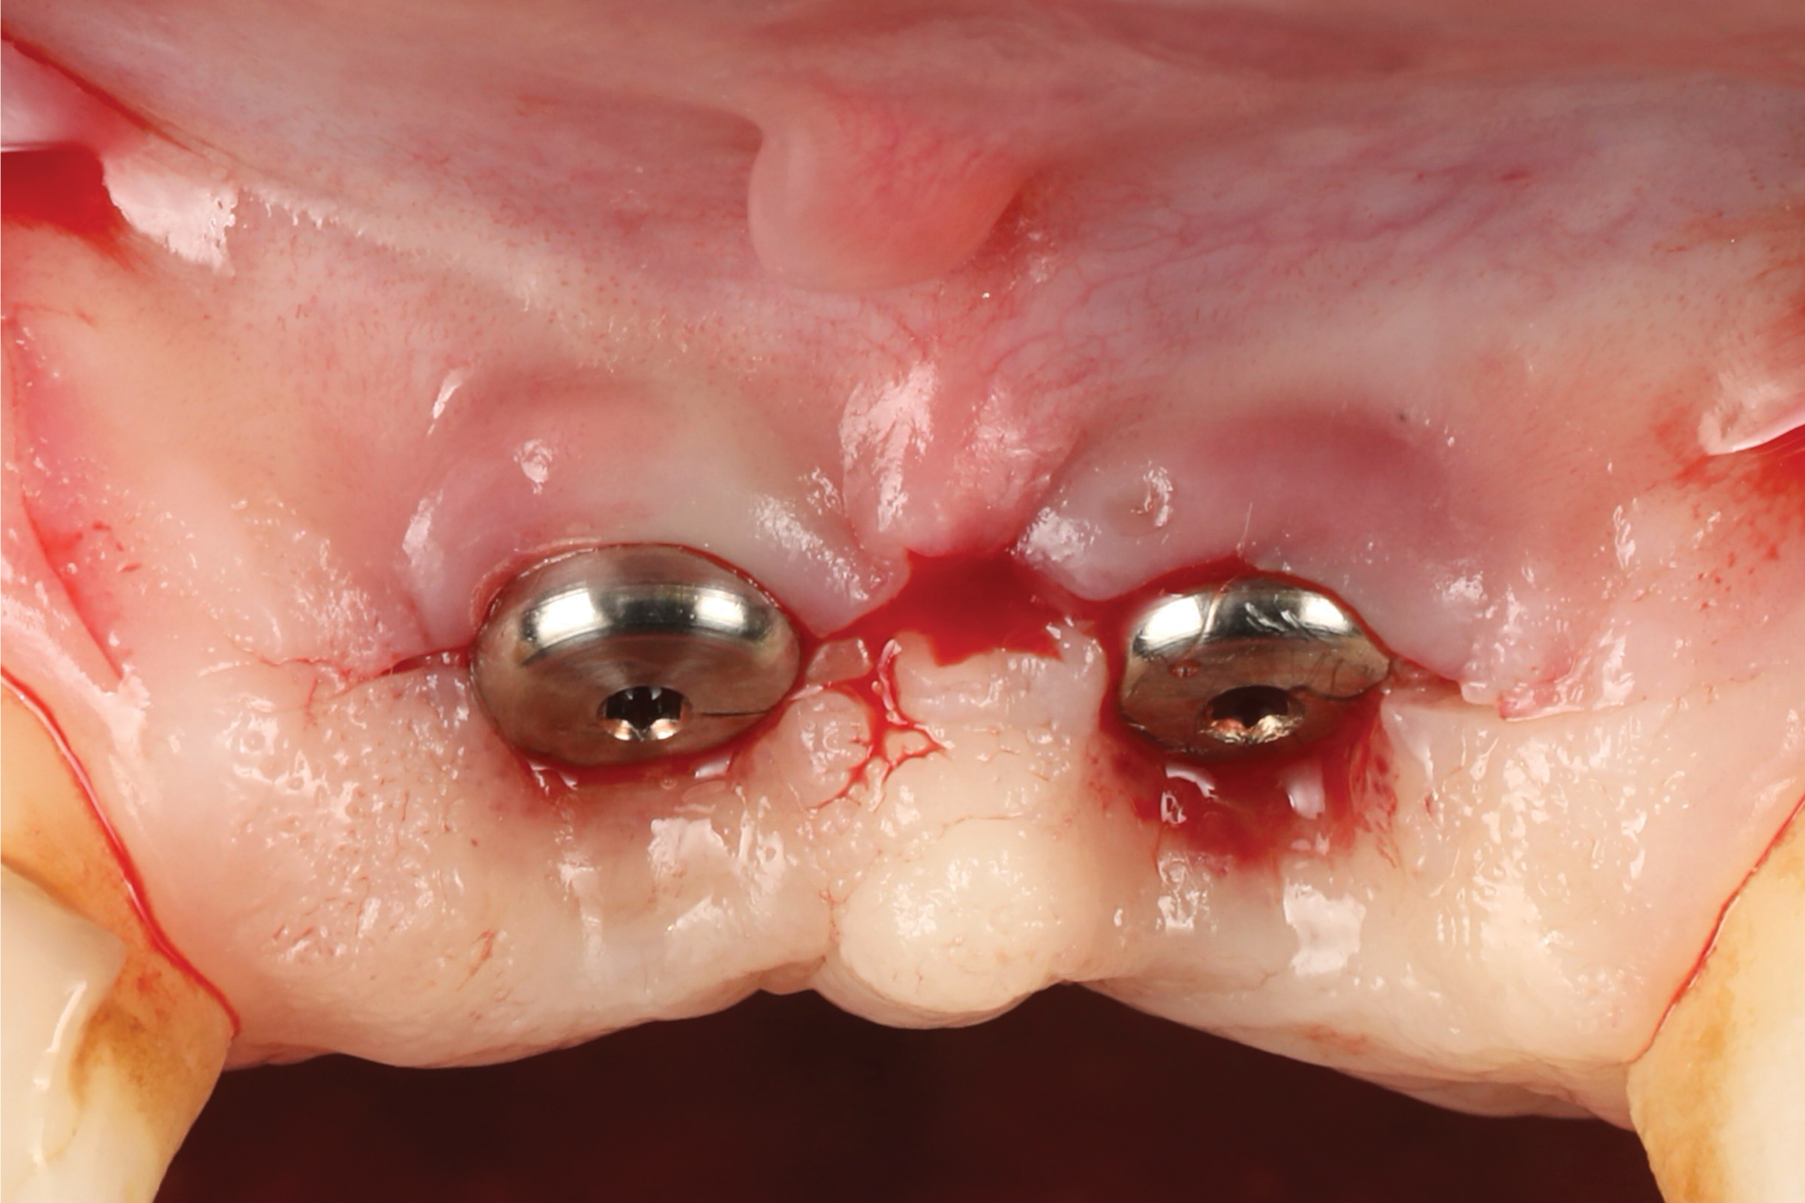

A 46-year-old systemically and periodontally healthy woman presented to the Graduate Periodontics Clinic at the University of Michigan School of Dentistry with the chief complaint of poor esthetics of her smile due to two dental implants (Nos. 8 and 9) showing their metal components (Figure 1). The patient reported that the implants had been placed 15 to 20 years previously after an accident. Clinical examination revealed that the implants had probing depths within 3 mm (facial probing depth of 3-2-3 mm for implant No. 8 and 2-2-2 mm for implant No. 9), no bleeding on probing, and no suppuration; the implants were therefore diagnosed as healthy (Figure 1 and Figure 2). The papilla between the two implants was deficient on the buccal aspect. The implants were buccally positioned, and a substantial lack of soft-tissue volume was noted.

Fig 1. Clinical view at presentation.

Figure 1